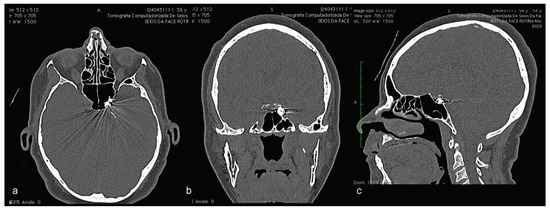

A computed tomography (CT) was performed in a fourchannel spiral CT scanner (Toshiba Asteion 4; Toshiba, Tokyo, Japan) with axial, coronal, and sagittal views. Multiple frac-tures were identified on the face (Figure 2 and Figure 3) and on the left side of the SS region (Figure 4).

Figure 2.

(a–d) CT windows displaying multiple fractures in the middle third of the face or midface.